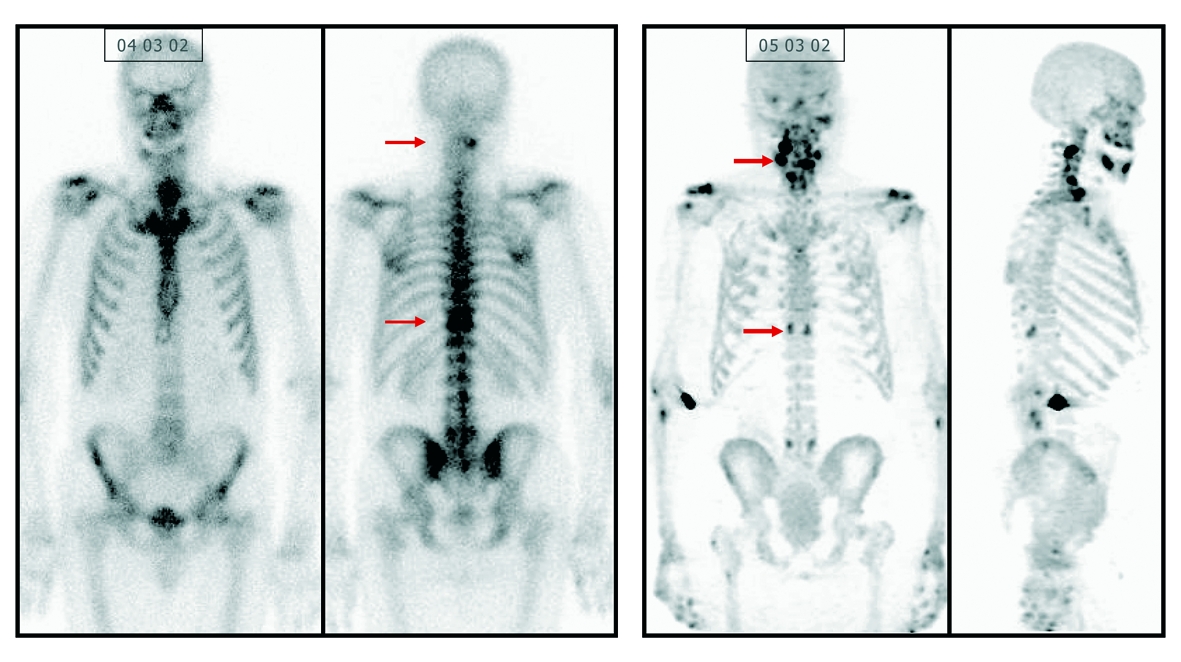

Das Nukleararzneimittel IASOflu(R) wird für funktionell

bildgebende Verfahren, zur Untersuchung von ungewöhnlichen Änderungen

der osteogenen Aktivität, indiziert. Das revolutionäre Fluorid

liefert exaktere Ergebnisse und unterstützt durch seine feinere

Detaildarstellung die Arbeit der Ärzte. Die IASON GmbH, Hersteller

Durch die Verabreichung von IASOflu(R) können Knochenmetastasen

bei Erwachsenen leichter lokalisiert und lebensrettende Maßnahmen

rascher eingeleitet werden. Weiters dient es zur Diagnose von

Rückenschmerzen mit zweifelhafter Herkunft. Diese Möglichkeit ist bei

konventionellen bildgebenden Verfahren nicht gegeben. Ein besonderes

Augenmerk gilt dem Einsatz von IASOflu(R) bei der Diagnostik von

Knochenläsionen mit Verdacht auf Misshandlungen bei Kindern. Gerade

in diesem sensiblen medizinischen Bereich wird der Bedarf solcher

Diagnoseverfahren steigen.